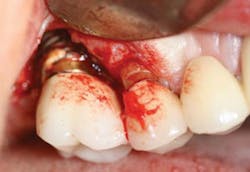

In writing about cement-associated peri-implantitis, I cannot possibly cover everything that's been written about factors affecting etiology, problems with various cements, or time frames of presentation of peri-mucositis or peri-implantitis. Instead, I focus on hygiene-related management issues (see Figure 2) that pertain to cement assessment. Keep in mind that the health of periodontal tissues is always dependent on properly designed restorations, and only with advanced study by implant clinicians can this growing problem be addressed.

3. Follow the AAP report in assessing peri-implant disease with emphasis on periodontal probing/exploring to look for signs of suppuration or cement residue. Blow air around the inflamed implant and explore carefully. If you have an endoscope, scope it thoroughly!

b. For cement-retained implant restorations, cement residue is often found around the entire circumference of the implant, making early detection of cement residue critical.6